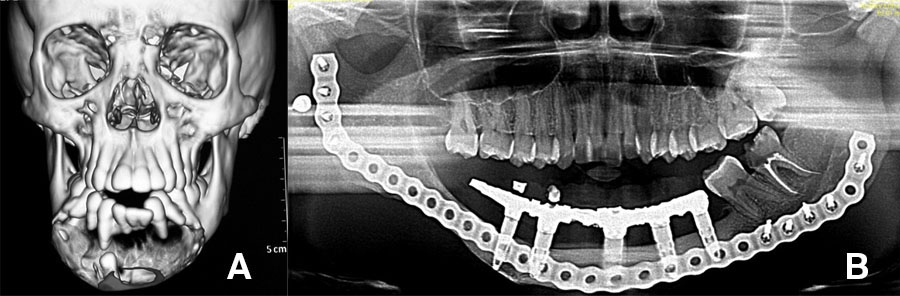

This is particularly useful in children with large defects. An example of such a case illustrated below: CT scan of 10-year-old with large ameloblastoma (A). Panoramic radiograph (B) 13 years post reconstruction and 7 years post implant placement and dental rehabilitation. Patient grafted at age 10 with a composite graft of autologous bone and TGF-β3 loaded onto DBM (demineralized bone matrix).

Images of 3D CBCT scan of patient with advanced osteomyelitis of the mandible (A). Virtual planning (B) is required to produce either a pre-bent or milled patient matched plate.